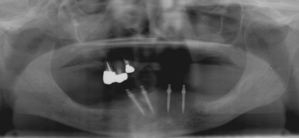

術後(鏡像)術後(鏡像)術後(鏡像) 術後口腔内(正面観)術後口腔内(正面観)術後口腔内(正面観)もう入れ歯は要らなくなりました。 術後レントゲン術後レントゲン術後レントゲン